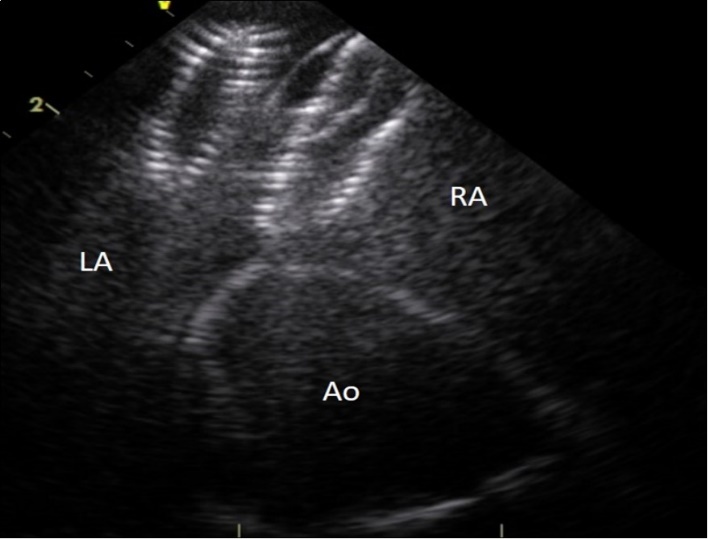

On examination, her heart rate was 71 beats per minute regular, blood pressure was 143/80 mm Hg, air saturation was 96% breathing ambient air and no fever. Jugular veins were not engorged. S1 and S2 were normal. There was a grade 3/6 ejection systolic murmur at right upper parasternal area. 24 hours ECG monitoring showed sinus rhythm. The neurological and pulmonary examination was normal. She underwent immediate transthoracic echocardiography and subcostal view showed a left-right shunt at the interatrial septum. Further evaluation revealed that the device embolized to the left ventricle and was lying in the left ventricular outflow tract with the distal extremity crossing the aortic ring. The device was displaced longitudinally with an important effect of stenosis. (Figure 1), (Figure 2). The entrapped device induced mechanical obstruction of the left ventricular outflow tract with a maximum/minimum gradients of 64/42 mmHg. The left ventricular function and size were normal. The mitral valve was normal with a minimal regurgitation. The right ventricle was mildly enlarged with normal function. The tricuspid valve function was normal. No pericardial effusion was detected. There was no gross thrombus deposition over the device in echography and no vegetation was detected anywhere.

Figure 2.Intracardiac ultrasound picture of the ASD Amplatzer device in place on the interatrial septum. RA :right atrium. LA:left atrium. Ao :aorta

Intracardiac ultrasound picture of the ASD Amplatzer device in place on the interatrial septum. RA :right atrium. LA:left atrium. Ao :aorta